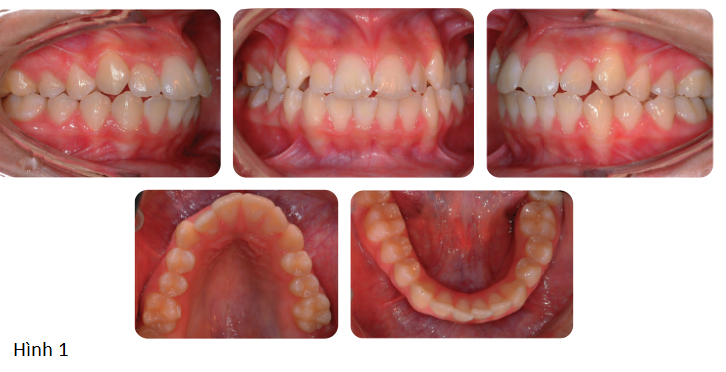

Kế hoạch điều trị (hình 3)

Mục tiêu điều trị là giải phóng chen chúc và giảm hô 2 hàm.

Tất cả 4 răng hàm nhỏ thứ nhất đều được nhổ để tạo khoảng trống và khí cụ edgewise có sẵn thông số được gắn vào. Sau giai đoạn làm đều đầu tiên bằng dây cung Niti tròn, dây thép không gỉ hình chữ nhật được đặt vào và nhóm răng trước được kéo lui bằng cách sử dụng chun nội hàm được hỗ trợ bởi thun kéo liên hàng hạng II ngắn.